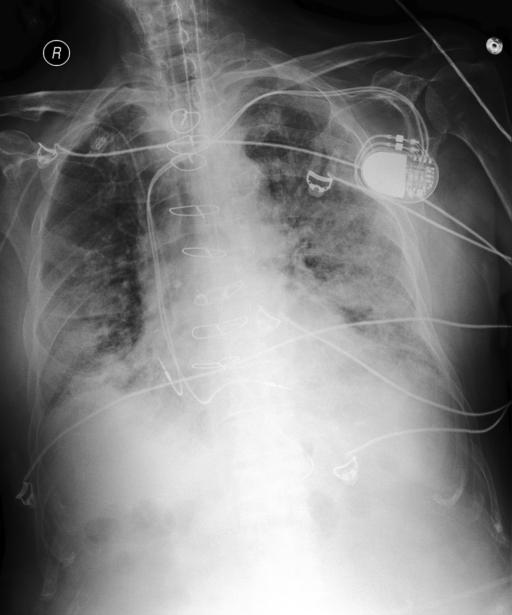

Refer to caption

Figure 1: Illustrative cases of medical hallucination include the following: (a) The model incorrectly answers a context-dependent medical question; the correct response should be “No.” (b) The model fabricates clinical knowledge, proposing “pleural effusion” and “asthma,” whereas the appropriate diagnoses are “lung cancer” or “pulmonary edema.” (c) The model hallucinates the nonexistent symptom “pleural effusions” and overlooks diffuse indistinctness of the pulmonary vasculature—a radiographic finding characteristic of “pulmonary edema”.